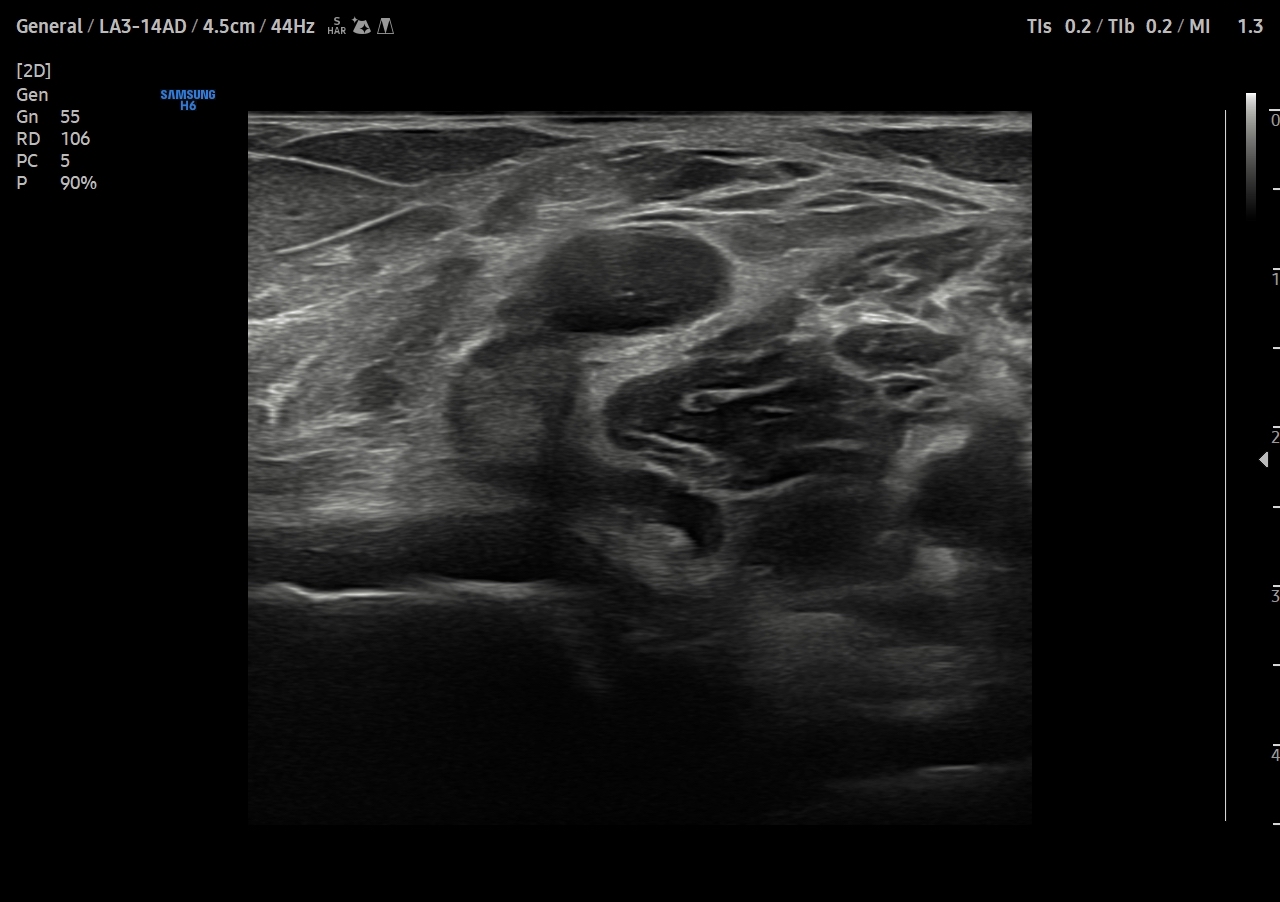

Se explora cara anterior, lateral y medial de rodilla sin hallazgos significativos. En cara posterior se explora el hueco poplíteo donde se visualiza en corte transversal una estructura hipoecoica con la base, el cuello entre el tendón del semimembranoso y el tendón de la cabeza medial del gemelo interno y el cuerpo. Sin signos de complicación. Permeabilidad del sistema venoso profundo.

Quiste de Baker.